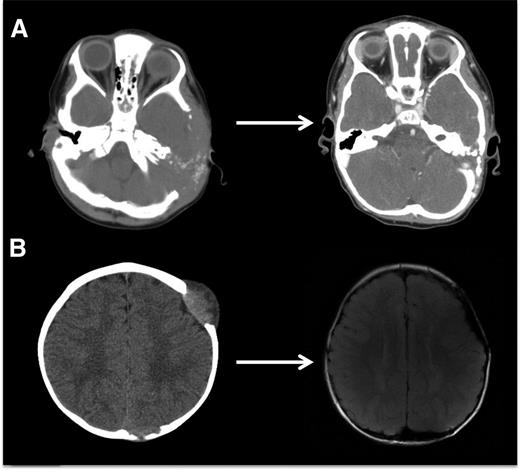

LCH bone lesions may remodel if margins remain intact. These cases highlight the potential for even very large bone lesions to remodel following disease resolution. (A) Skull CT scans before and after chemotherapy in a patient with multifocal bone LCH. Remodeling following systemic chemotherapy nearly normalizes bone structure in a patient with significant skull lesions. This patient did not have any curettage or excisional surgery in the skull. (B) Brain MRI in a patient with multifocal bone LCH before and after complete excision with placement of mesh grafts. Complete excision of LCH lesion with margins into healthy bone inhibits potential for remodeling. Following resections and successful chemotherapy, skull defects persist.